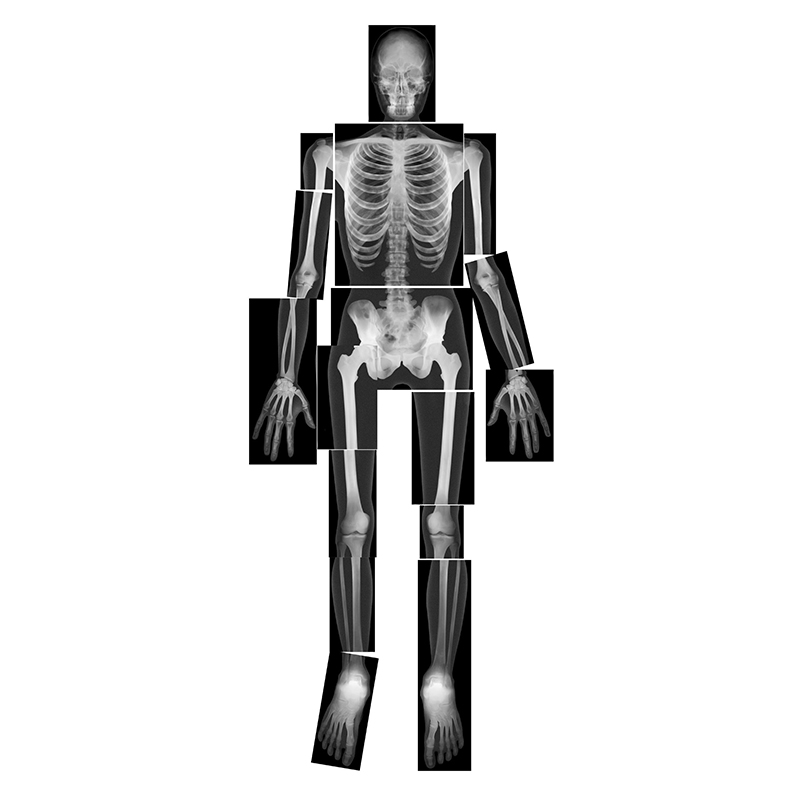

Product description

Hold these life-size human x-rays up to the light or use them on a light table and see every authentic detail of a real skeleton. Arrange the 18 pieces together to reproduce the entire body of a young adult 5' (1.5 m) tall. The teacher guide includes reproducible artwork and information on radiography. 18 pieces. Age 5+.